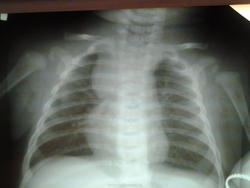

Ребенку 3 месяца, поступил в больницу с бронхитом, со слов матери кашель - давно. Состояние удовлетворительное, лимфоузлы шейные, подмышечные не пальпируются.

полная норма юскажу больше это так называемый сиптом зубца-так называемый угол,вершиной направленный в сторону средостения ,в месте пересечения выпуклой дуги вилочковой железы и выпуклой дуги седца ,образованного правым предсердием и левым желудочком!!!!!!2-3 месяц жизни

Тимомегалия. Тимома?

Не высоковато для вилочковой железы?

грудная клетка несколько повёрнута, по-видимому тимомегалия...

Согласен с тимомегалией. УЗИ?

Думаю, что это находится в пределах нормы - а субстрат - тимус.

Не стал бы утверждать, что увеличенная вилочковая железа - норма.